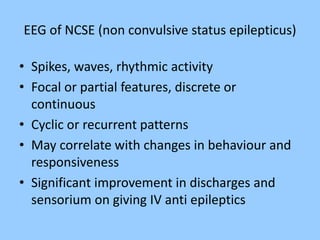

1. The document discusses EEG patterns and findings in various neurological conditions seen in children. It includes descriptions of normal EEG findings as well as abnormal patterns seen in conditions like absence seizures, West syndrome, benign childhood epilepsy with centrotemporal spikes, Lennox-Gastaut syndrome, non-convulsive status epilepticus, subacute sclerosing panencephalitis, and herpes encephalitis.

2. Case studies are presented with clinical histories and EEG findings to illustrate different pathologies. Treatment options are also mentioned for many of the conditions.